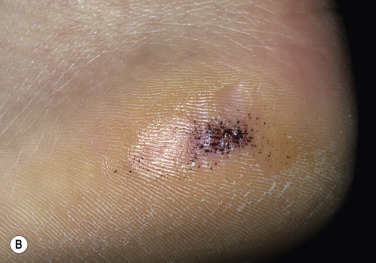

Black Warts.

Warts in the process of undergoing spontaneous resolution, particularly on the plantar surface, may turn black ( Fig. 12.23 ) and feel soft when pared with a blade. Cell-mediated immunity against virus-infected keratinocytes may take place in the process of regression of some warts.